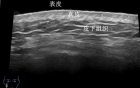

【五院科普】超高频皮肤超声:皮肤检查的 “隐形放大镜”

发布时间:2025-11-18